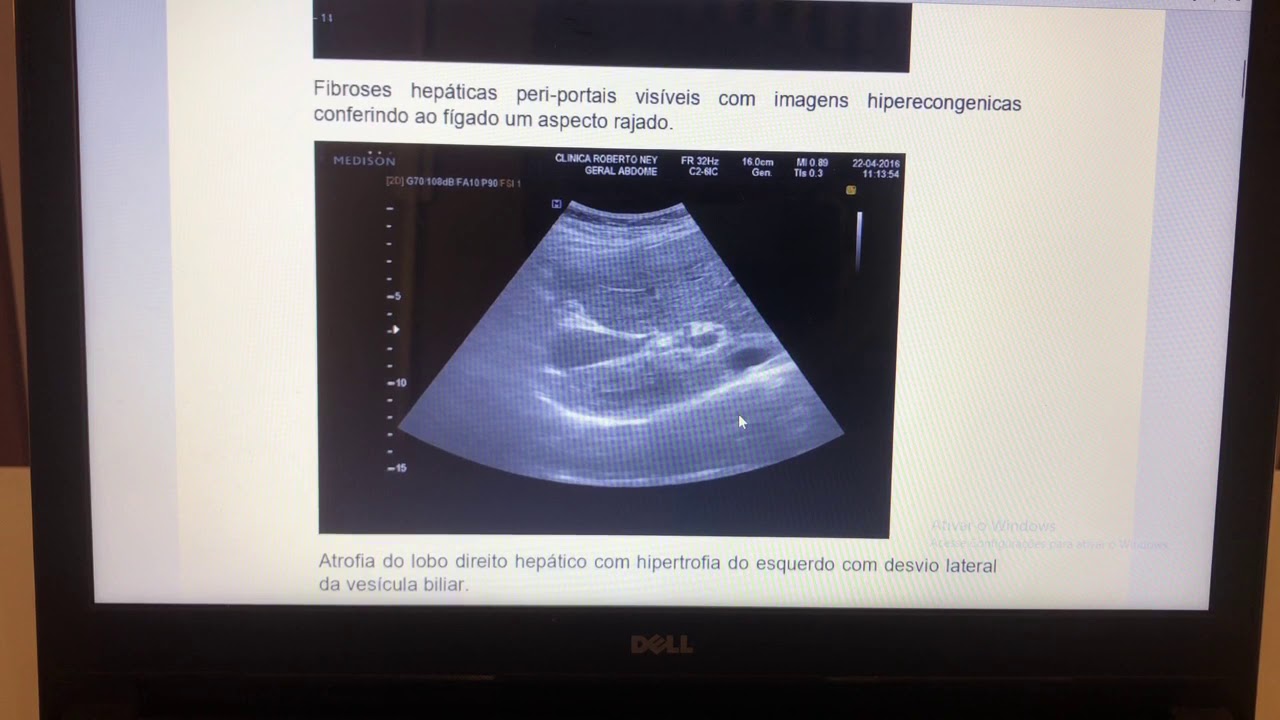

de fibrose em torno nos ovos no fígado essas áreas de fibrose concentra-se em torno dos capilares do espaço porta onde grande quantidade de ovos é retida e esse padrão de fibrose periportal recebe o nome de fibrose de symmers bom então pessoal é por causa dessa fibrose gerada ao redor do ovo que vai fazer com que todo o sistema passa a funcionar com maior pressão ou seja o sangue que precisa passar pelo fígado vai encontrar certa resistência e com isso aumenta a pressão nessas veias por isso nós temos a hipertensão Portal daí como consequência o baço

que pode auxiliar o diagnóstico da fibrose no fígado né na como eu falei assim prosa de Simas e também pode auxiliar nos casos de hepatoesplenomegalia nós temos a radiografia de tórax que pode ser útil no caso de hipertensão pulmonar nós temos a endoscopia e pode ser usada nos casos de varizes esofágicas em nós temos também ressonância magnética que pode ser empregada nos casos né de mielopatia Ou seja quando nós temos a infecção nos órgãos do sistema nervoso central a unha existe ainda a possibilidade da detecção de do DNA né de ácidos nucleicos do parasito por